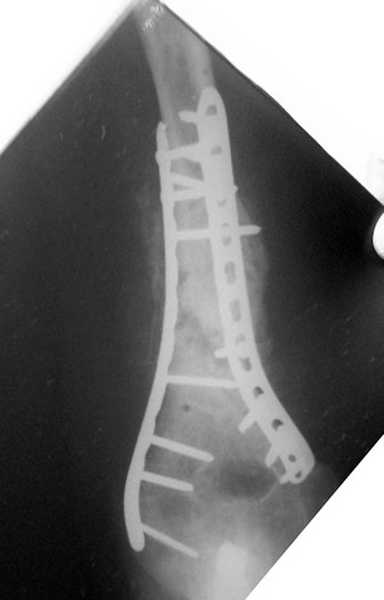

Второй случай, также после множественных операций:

пластина, аппарат, серкляж и парез нерва.

Также ревизия, из-за низкого состояния доступ был

сделан через остеотомию локтевого отростка.

Ложный сустав фиксирован двумя локинг плейт с

аутокостной пластикой, также через два месяца увидели признаки консолидации.

Движение в суставе разрешили в две недели.